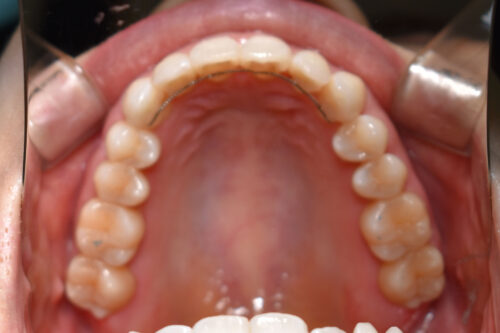

歯のがたつき(叢生)と過蓋咬合を非抜歯矯正治療で治した症例(かみ合わせ変化10か月)

初診時年齢 27歳 女性

歯のでこぼこ(叢生)

と

過蓋咬合

を主訴に

右側が アングル2級とよばれる

出っ歯傾向の状態で

上の正中が

半歯分 ずれている状態でした。

また 下あごの 歯が見えず

過蓋咬合を呈していました。

ワイヤー矯正治療10か月後です。

本症例も

上顎左右臼歯部に

歯科矯正用アンカースクリュー(デュアル・トップオートスクリュー)を用い

下あごを オートローテーションさせ

また 上下の歯列全体を

後方へ移動させることで

歯を抜かなくても

口元の改善も行いました。

上下の正中には 若干ずれが残存しましたが、

かみ合わせ重視で

終了いたしました。